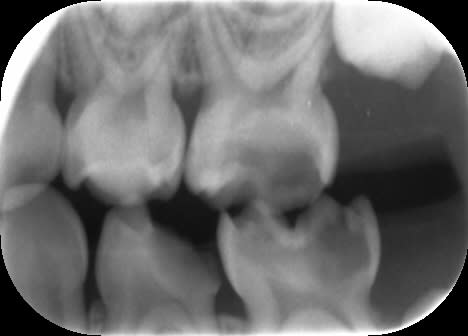

Radios de contrôle.

Pour 65, on voit sur la vue clinique une large canal palatin ovalaire. L'image radiographique correspond probablement à la fusée d'IRM dans l'entrée de ce canal. Je ne pense pas avoir perforé (j'espère !).